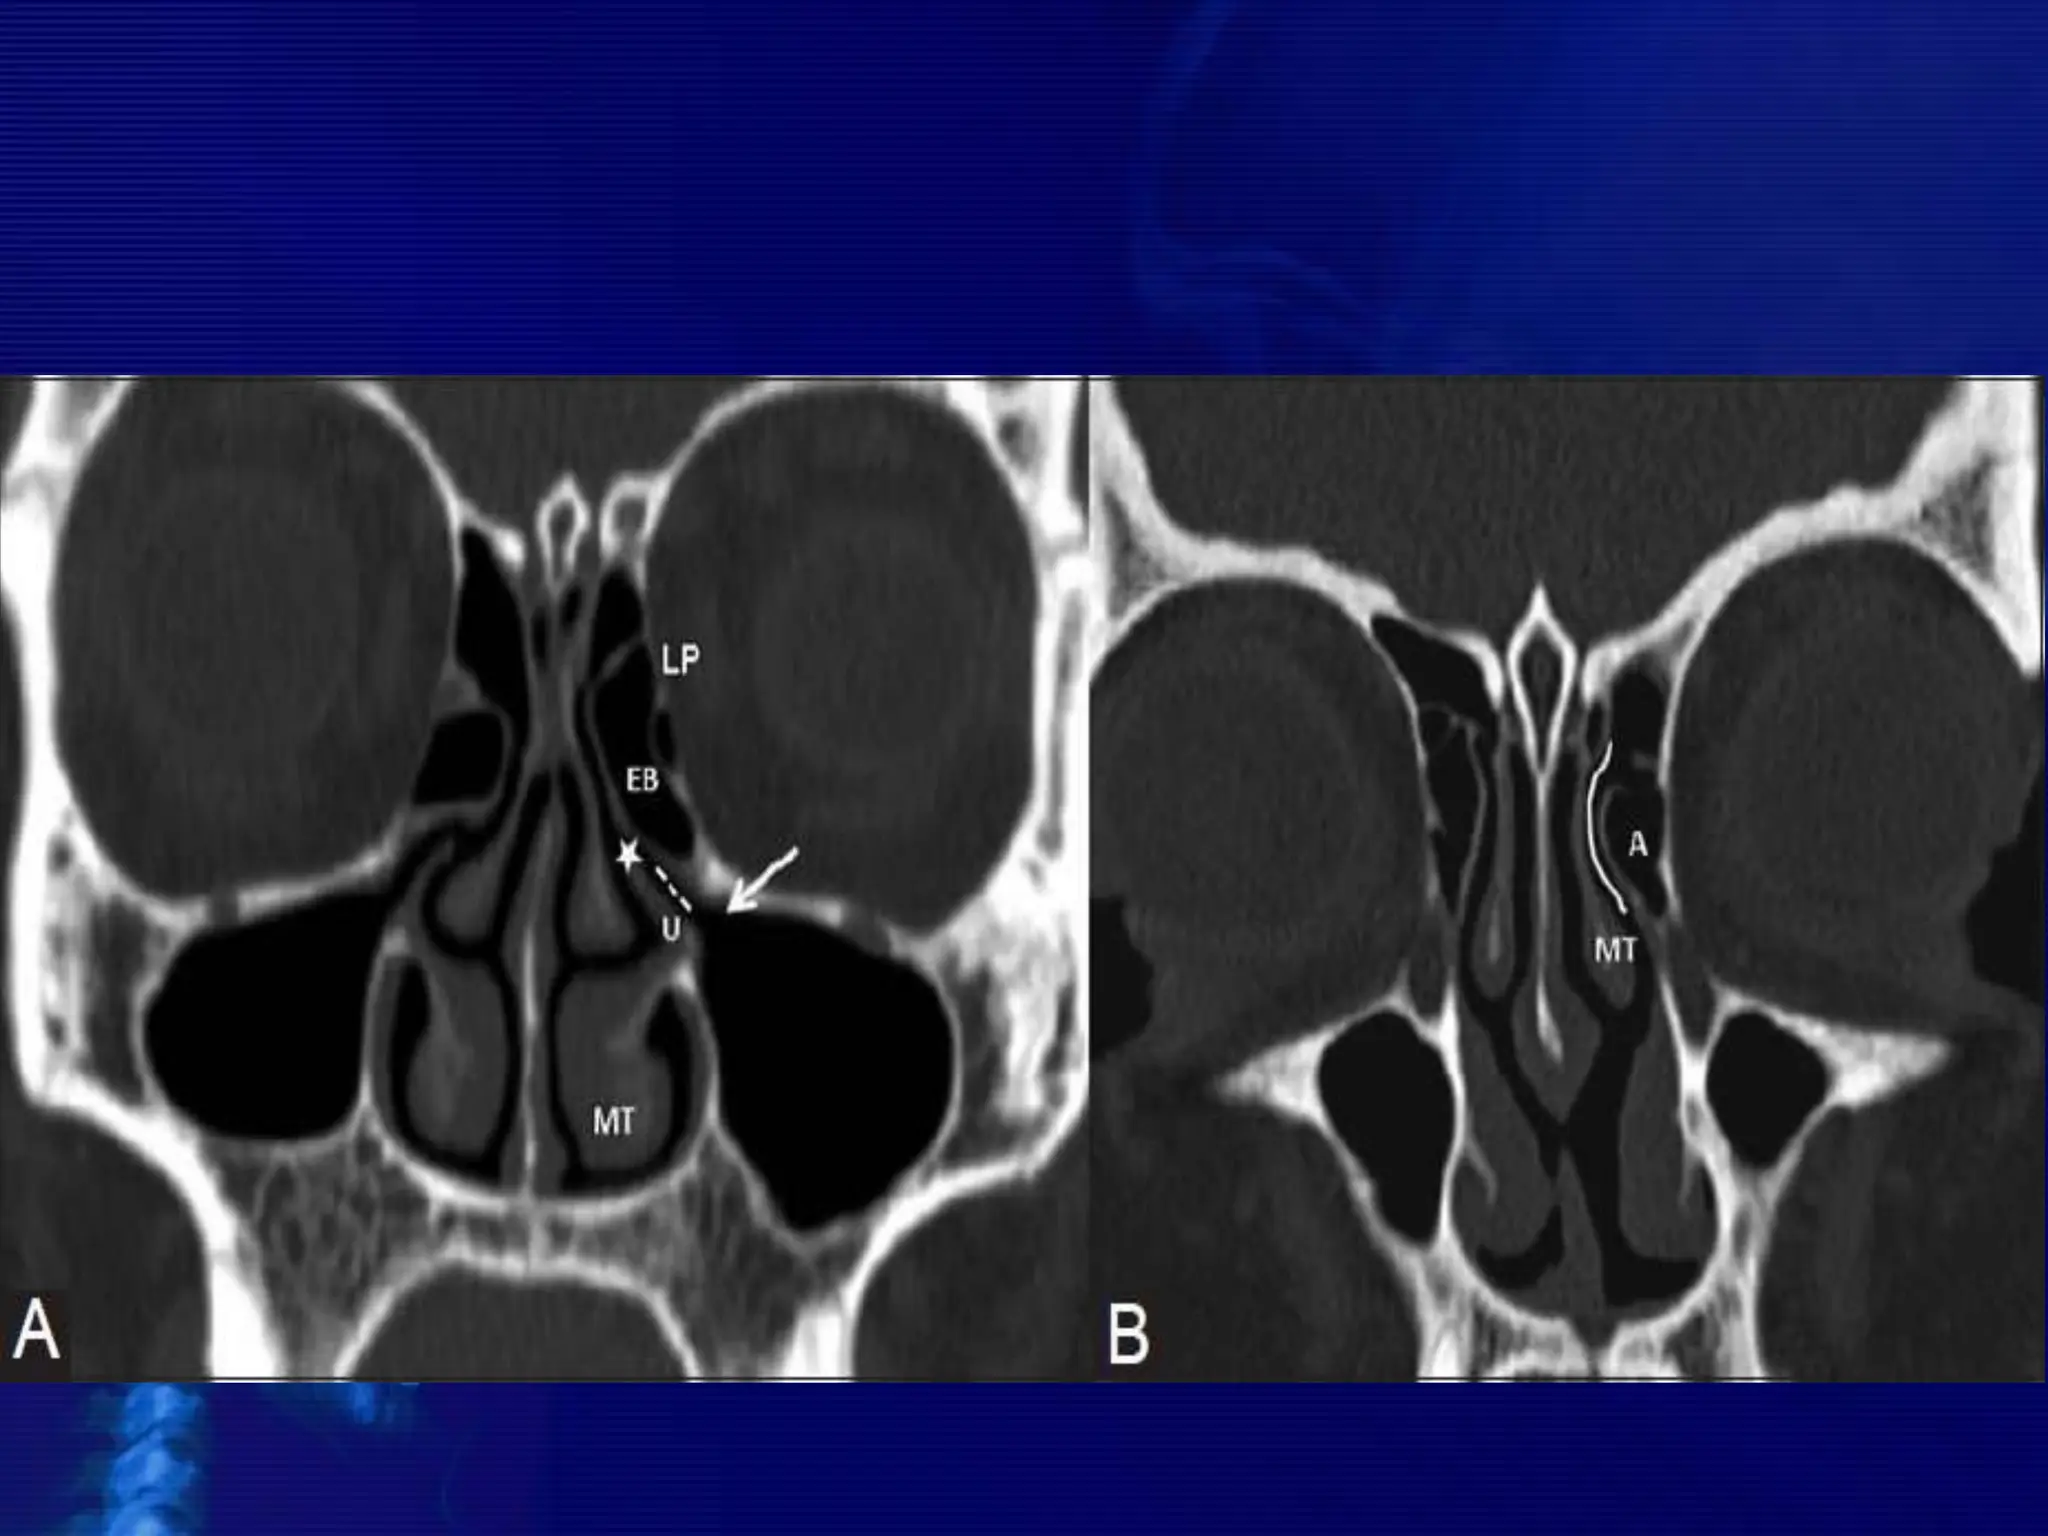

• #8 Figure 1 (A, B): (A) Coronal CT scan shows the osteomeatal complex which comprises of - infundibulum (dotted line), hiatus semilunaris (asterisk), maxillary ostium (arrow) and Ethmoidal bulla (EB). MT-middle turbinate, LP-lamina papyracea. (B) Coronal CT images reveals a prominent agger nasi cell (A) inferior and lateral to the nasofrontal recess (solid curved line). The medial relationship of the recess is formed by the middle turbinate (MT)

Osteomeatal unit

• The osteomeatal unit (OMU) includes the (1) maxillary

sinus ostium, (2) ethmoid infundibulum, (3) anterior

ethmoid air cells, and (4) frontal recess.

• The OMU is the key factor in the pathogenesis of chronic

sinusitis.